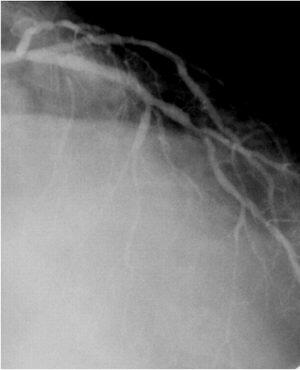

S670を植え込んだほぼ1年後に、血栓性の閉塞を来したAMI症例を経験したこと

画像のPCI-1、2、3は1stPCIで1年後のAMI、resque後、stenting後となっています。

resqueでは血栓が引けたように記憶しています。